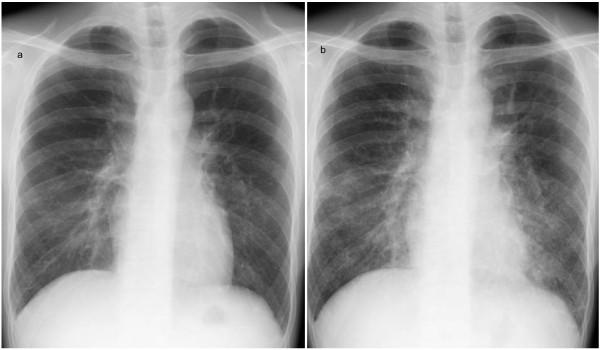

A 36-year-old Japanese man, who had been diagnosed with Epstein-Barr-virus-induced infectious mononucleosis, new-onset systemic lupus erythematosus, and secondary Sjögren's syndrome three weeks previously, presented to our facility with fever and diffuse pulmonary infiltrates. A computed tomography scan of the chest revealed multiple small nodules in both lungs. Fiberoptic bronchoscopy with bronchoalveolar lavage revealed lymphocytosis with predominance of T lymphocytes. A histological examination of a lung biopsy taken during video-assisted thoracic surgery showed randomly distributed tiny granulomatous lesions with infiltration of eosinophils. The differential diagnoses included hypersensitivity pneumonitis, sarcoidosis, and pulmonary involvement of Crohn's disease, systemic lupus erythematosus, and Sjögren's syndrome, but the clinical and pathological findings were not consistent with any of these. Our patient's condition did not improve; therefore, prednisolone therapy was started because of the possibility of specific immunological reactions associated with Epstein-Barr virus infection. After steroid treatment, our patient showed radiological and clinical improvement.

一名36岁的日本男性,三周前被诊断为EB病毒引起的传染性单核细胞增多症、新发系统性红斑狼疮和继发性干燥综合征,因发热和双肺弥漫性浸润前来我院就诊。胸部计算机断层扫描显示双肺有多个小结节。纤维支气管镜检查及支气管肺泡灌洗显示淋巴细胞增多,以T淋巴细胞为主。电视辅助胸腔镜手术中获取的肺活检组织学检查显示有随机分布的微小肉芽肿性病变,伴有嗜酸性粒细胞浸润。鉴别诊断包括过敏性肺炎、结节病以及克罗恩病、系统性红斑狼疮和干燥综合征的肺部受累,但临床和病理表现均不符合上述任何一种情况。我们患者的病情没有改善;因此,鉴于可能存在与EB病毒感染相关的特异性免疫反应,开始使用泼尼松龙治疗。激素治疗后,患者的影像学和临床症状均有改善。